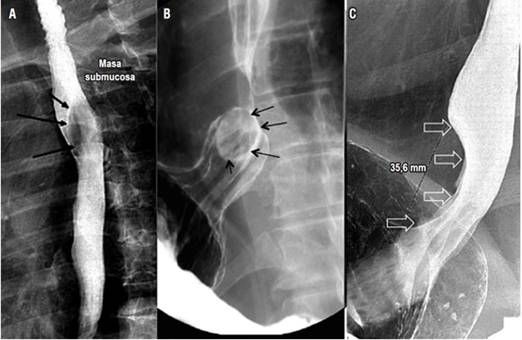

Tumores benignos del esófago

El esofagograma es un estudio de gran utilidad para la detección, localización y medición de lesiones estenosantes, tanto benignas como malignas, con una sensibilidad del 95% para la detección de estrecheces de la luz esofágica 13. Los quistes de duplicación son alteraciones congénitas infrecuentes del desarrollo del tracto digestivo consideradas el tercer tumor benigno más frecuente del esófago, después de los pólipos y el leiomioma. En adultos, su hallazgo es incidental, su localización más frecuente es el mediastino derecho posteroinferior y su tratamiento es generalmente quirúrgico, incluso en ausencia de síntomas 24,25 (Figura 9).

Los pólipos fibrovasculares son tumores subepiteliales e intraluminales de lento crecimiento que, generalmente, se localizan en el esófago proximal, se presentan con pedículos largos -los cuales crecen distalmente- y el pólipo puede encontrarse distal a su sitio de implantación. La resección endoscópica o quirúrgica representa una opción terapéutica en pacientes con síntomas 26,27 (Figura 9).

El leiomioma es el tumor benigno más común del esófago y, usualmente, se localiza en el tercio inferior del esófago y de forma intramural. Estos tumores se presentan con disfagia y dolor torácico, y son masas generalmente móviles no obstructivas que rara vez causan dilatación esofágica. La cirugía está reservada para los pacientes sintomáticos 27 (Figura 9).